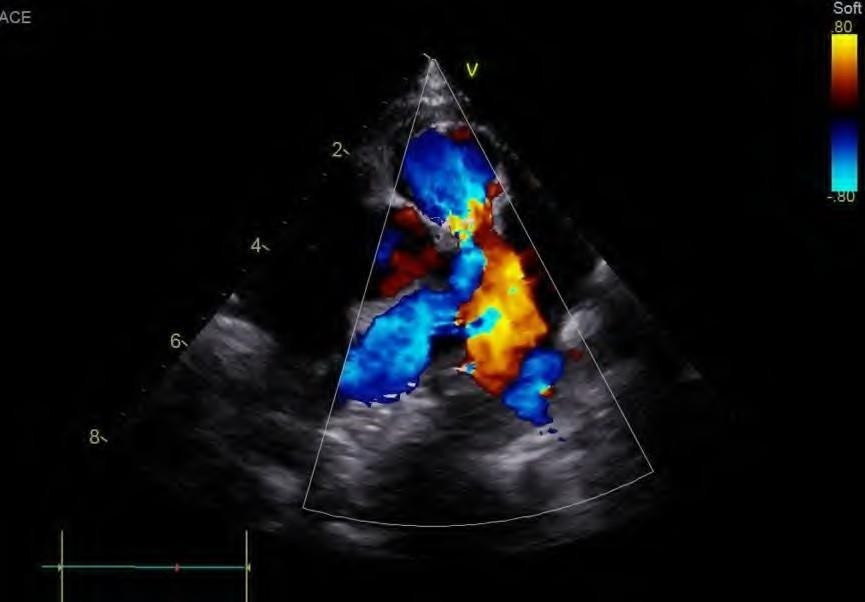

He underwent a new hybrid cardiac operation with patch closure of the atrial septal defect, closure of the VSD with a device, repair of the left and right atrioventricular valve. The device was positioned after right atriotomy and under direct vision, through the tricuspid valve. The device had a diameter of 5mm. An Amplatzer Duct Occluder II (size9-2-6-4) was used with disc diameter of 12mm, a waist diameter of 6 mm, and a waist length of 4 mm (Figure 1B). A device charging system was used but with a short 6 Fr sheath as a release system.